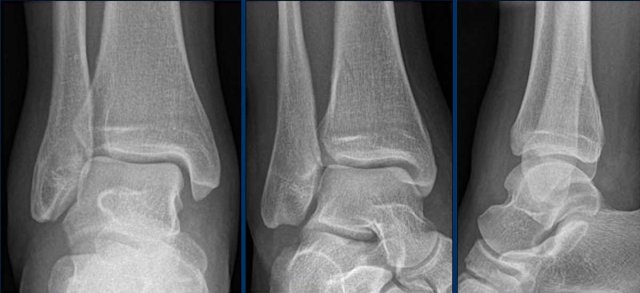

case 4 - ankle distortion

What are the findings?

What is the stage of this injury?

Click on the image for larger view.

Go to the discussion...